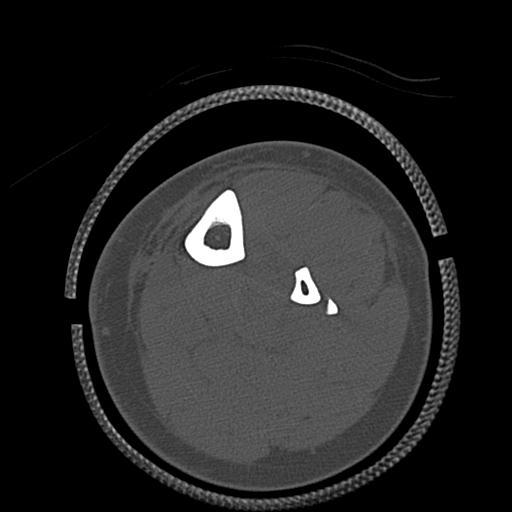

49554 3/13 膝 4R 3/16 4R 1/18 2R 78歳男性 膝蓋骨骨折